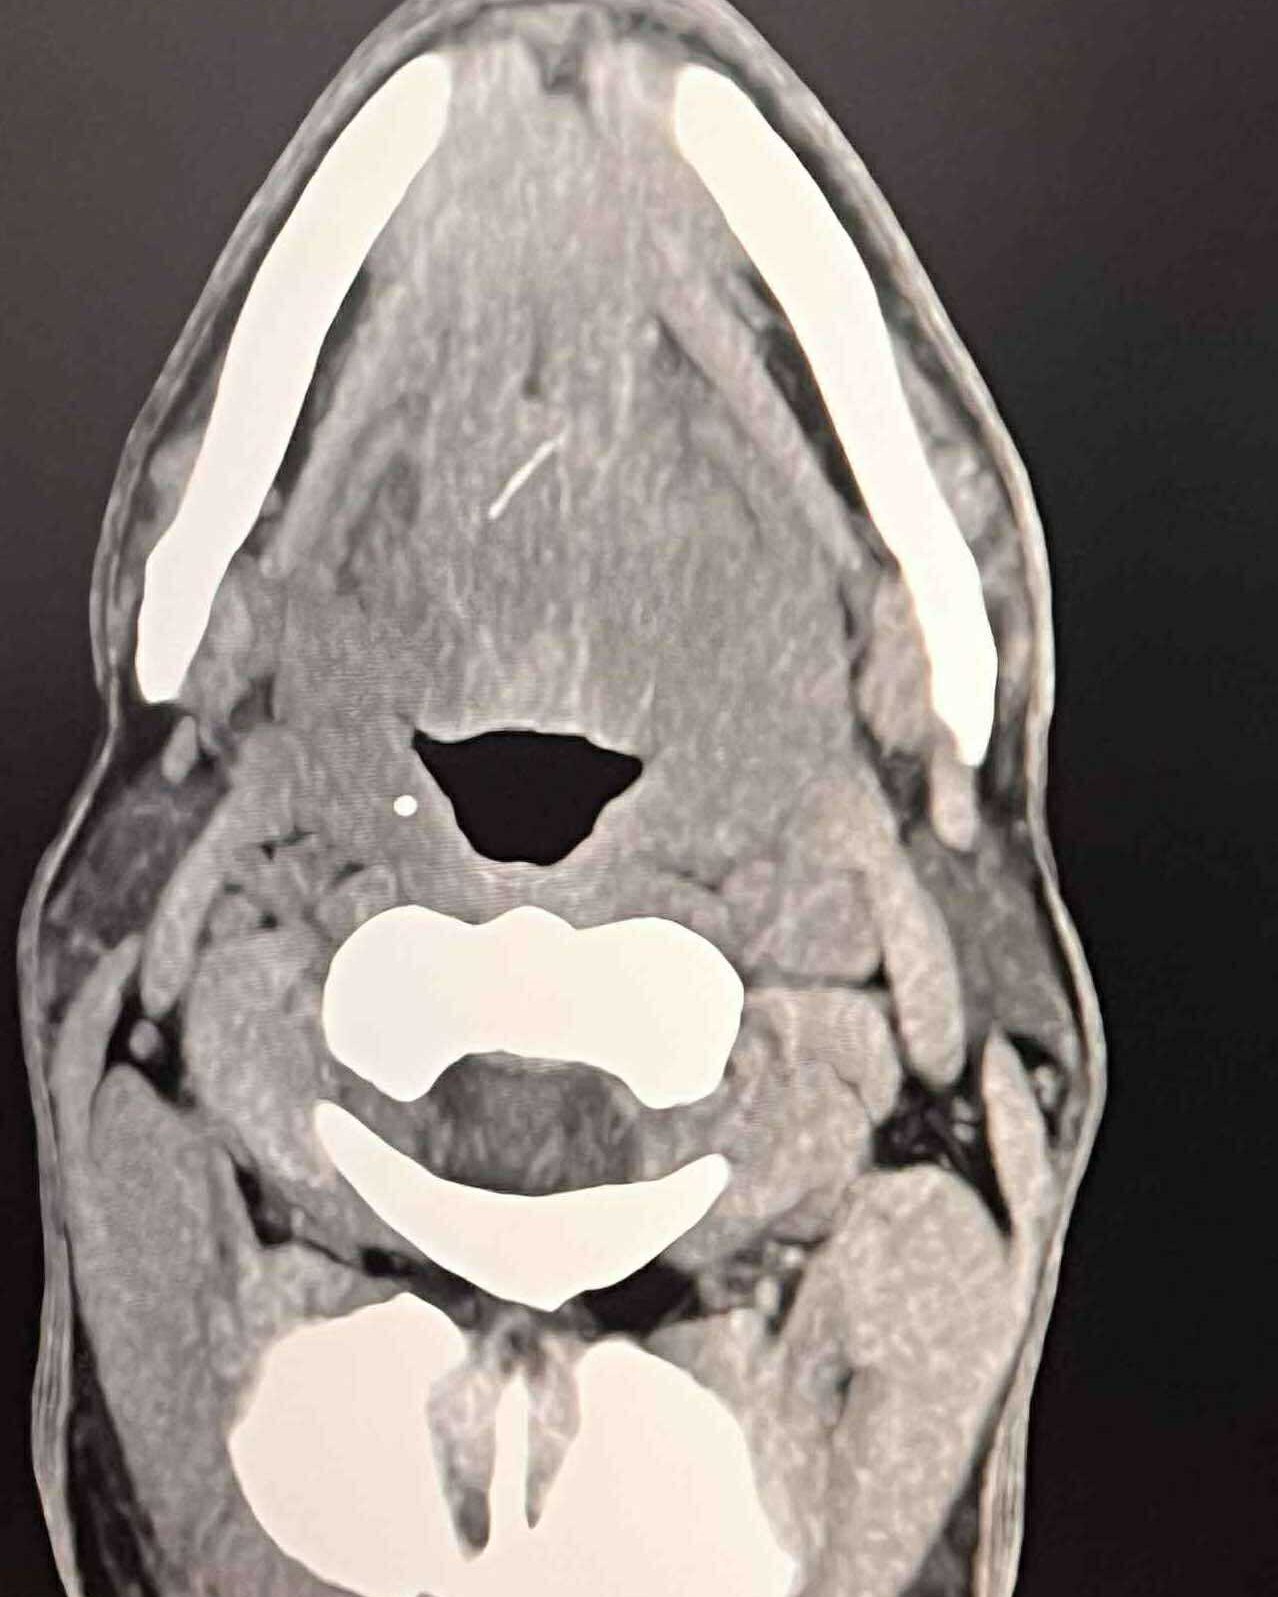

Прегледът открива: издут и мъчителен език, затруднено преглъщане, наложително отворена уста и щедро слюноотделяне. Компютърната томография разкрива тънка 12-милиметрова конструкция, наподобяваща рибена кост, забита надълбоко във вътрешните мускули на езика и цирей в съседство - празнина, цялостна с гной.

Снимка: Фейсбук